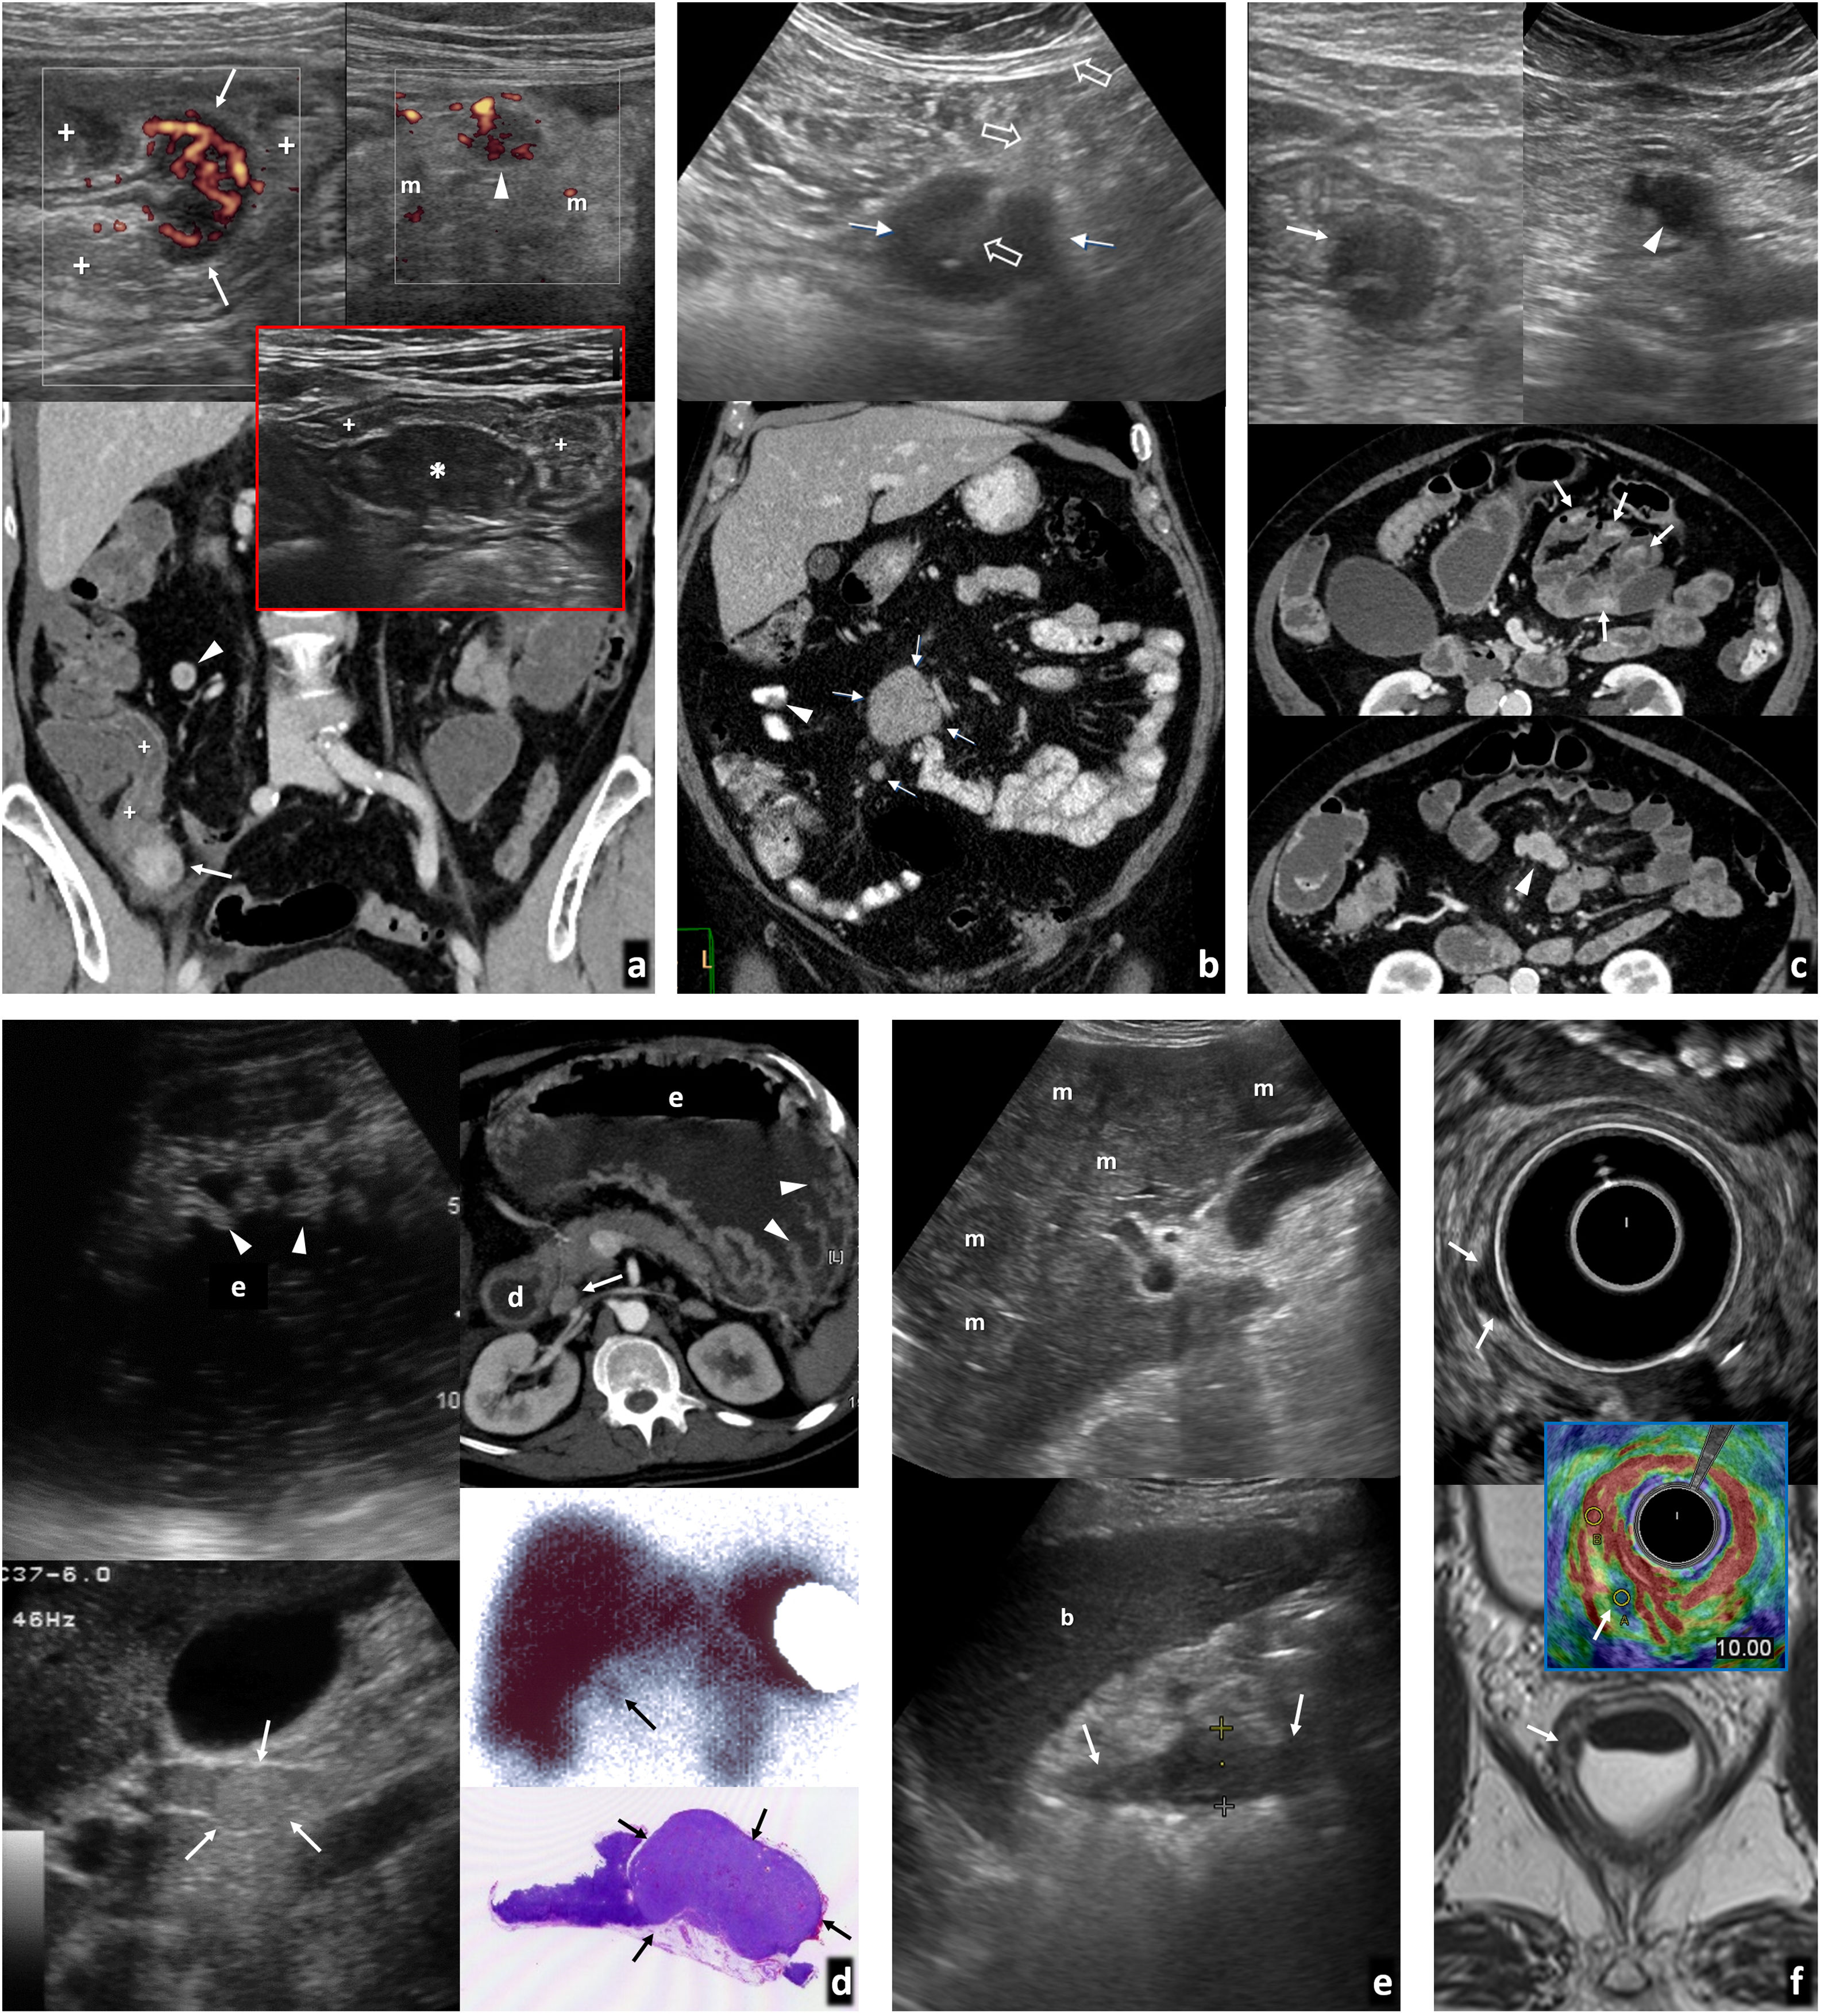

Tumores neuroendocrinos (TNE) (fig. 6, vídeo 2)Los gastrointestinales asientan generalmente en la capa submucosa. La OMS los considera potencialmente malignos, estableciendo tres grados de agresividad según la proliferación celular. Dentro del grupo G3, los tumores con Ki-67 >50 son carcinomas. Pueden aparecer en síndromes genéticos (MEN-1, von-Hippel-Lindau, esclerosis tuberosa y neurofibromatosis-1). Muchos segregan hormonas o aminas que condicionan el cuadro clínico y facilitan la detección analítica (serotonina o derivados, cromogranina-A, gastrina, sinaptofisina, enolasa específica neuronal, etc.) o con procedimientos de medicina nuclear (destacando la PET-TC con 68Ga-DOTATATE por la expresión del receptor SSTR2 en tumores diferenciados, quedando la PET-TC con 18FDG para valorar la actividad metabólica en desdiferenciados)55–57.

Tumores neuroendocrinos. A) Tumor carcinoide de íleon terminal. Mujer de 62 años con vómitos y dolor abdominal. Antecedente de macroadenoma hipofisario intervenido. Imagen superior: ecografía. Imagen inferior: tomografía computarizada (TC) coronal. Lesión nodular hipoecogénica con abundante vascularización en Doppler y TC (flechas), en el ángulo interno de tramo plegado de íleon distal (+), con peristaltismo ineficaz a tiempo real (vídeo 2). Además, adenopatías hipoecogénicas y vascularizadas (cabezas de flecha) en meso regional tumefacto y ecogénico (m). Se diagnostica MEN-1. En el recuadro: implante endometriósico (*) en íleon terminal (+) en otra paciente, como nódulo hipoecogénico que infiltra la serosa, retrayendo el asa y respetando las capas profundas, que muestra hallazgos similares y con el que hay que establecer diagnóstico diferencial (no vascularizado y sin afectación adenopática en este caso). B) Carcinoide ileal solo manifestado como masa mesentérica. Imagen superior: biopsia percutánea (flechas huecas) guiada ecográficamente de nódulo mesentérico hipoecogénico (flecha), que demostró metástasis ganglionar de tumor neuroendocrino. Imagen inferior: TC coronal con contraste oral e intravenoso. Nódulos adenopáticos mesentéricos (flechas). En la cirugía se identificó un carcinoide milimétrico intestinal primario y retrospectivamente podría corresponder al pequeño defecto de repleción indicado por la cabeza de flecha. C) Carcinoides yeyunales múltiples y metástasis ganglionares mesentéricas. Mujer de 71 años con molestias abdominales inespecíficas. Imágenes superiores: ecografías. Centrales e inferiores: imágenes axiales de entero-TC en dos planos diferentes. Se detectan hasta 5 tumores hipoecogénicos e hipervasculares (uno no mostrado) en tramos plegados de yeyuno (flechas), con un pequeño conglomerado adenopático también hipervascular e hipoecogénico en el meso tributario (cabezas de flecha). D) Síndrome de Zollinger-Ellison por tumor neuroendocrino de tipo II (gastrinoma) de tracto digestivo superior. Varón de 44 años con vómitos, diarrea y shock. Imagen izquierda: ecografía. Imagen derecha superior: TC axial. Abundante líquido en estómago (e), duodeno (d) y yeyuno proximal (no mostrado), con marcado engrosamiento de pliegues gástricos (cabezas de flecha). Medial al duodeno y posterior al páncreas se ve un nódulo hipervascular y levemente ecogénico (flechas) en el seno de una estructura ganglionar. Esta región está dentro del llamado “triángulo del gastrinoma”. Derecha centro: gammagrafía con octeótrida. Se confirma captación por parte del nódulo (flecha). También hay hipergastrininemia. Derecha inferior: pieza quirúrgica del gastrinoma (flechas) en el seno de un ganglio. E) Carcinoma neuroendocrino gástrico de tipo III. Varón de 59 años con síndrome constitucional. La ecografía muestra abundantes metástasis hepáticas (m) y, empleando el bazo (b) como ventana acústica, un tumor infiltrante en la curvatura mayor del estómago. Se sospechó un adenocarcinoma, pero la biopsia endoscópica demostró un carcinoma neuroendocrino. F) Tumor neuroendocrino rectal. Hallazgo en la colonoscopia por test de sangre oculta en heces positivo en varón de 62 años. Imagen superior: ecografía transrectal. Imagen inferior: RM T2 axial. Tumor de 7× 5 mm (flechas) con comportamiento hipoecogénico e hipointenso en T2, situado en la parte profunda de la capa submucosa del recto inferior, con moderada rigidez tisular en elastografía (recuadro central), con strain ratio de 10 con respecto a la pared rectal normal. Se realizó una resección endoscópica transanal.

Los más frecuentes son los carcinoides de íleon distal, donde suponen la neoplasia más habitual. Es un tumor submucoso pequeño (15-35 mm), hipoecogénico o con halo ecogénico35,37,56. La secreción de serotonina hace que pueda provocar obstrucción por retracción intestinal. La endometriosis puede simularlo35. Tiende a extenderse al mesenterio como adenopatías discretas o en forma de masas desmoplásicas hipoecogénicas, con frecuentes calcificaciones, que pueden ser el hallazgo dominante y provocar congestión mesentérica y del intestino tributario35,36,55,56. La ecografía detecta el 13-76,5% de los tumores primarios (26-40% múltiples)55,56. Tanto estos como las metástasis ganglionares o hepáticas realzan intensa y precozmente, a veces periféricamente35,58. La intensidad y el patrón de realce y lavado se han correlacionado con el grado tumoral58.

En duodeno y yeyuno proximal son muy infrecuentes. Pueden darse carcinoides o gastrinomas55,59, en cualquier caso, con adenopatías habituales y comportamiento menos desmoplásico. Los TNE suponen un 1% de las neoplasias gástricas. Los de tipo I (70-80%) son secundarios a gastritis crónica atrófica, no invasivos y pequeños. Los de tipo II (5-6%) son gastrinomas, también no invasivos y pequeños, y pueden producir síndrome de Zollinger-Ellison. Los de tipo III (15-20%) son invasivos y agresivos, simulando adenocarcinoma55,56.

El recto es la segunda localización de TNE gastrointestinales. Son pequeños y localizados, con buen pronóstico56. En ETR aparecen como hipoecogénicos, circunscritos a la submucosa.

Los TNE colónicos son muy raros y agresivos, si excluimos los apendiculares (donde representan el 60% de tumores), hallazgo incidental en pieza de apendicectomía en un 70% de los casos56, en general con buen pronóstico.

GIST y otros tumores mesenquimales (fig. 8)El GIST, derivado de la célula intersticial de Cajal, es ampliamente la neoplasia mesenquimal gastrointestinal más frecuente, asentando generalmente en la capa muscular. Aproximadamente el 60% afectan al estómago, el 30% al intestino delgado y el 4% al colon-recto. La edad media al diagnóstico es de 60 años, menor en contextos sindrómicos (síndrome de Carney-Stratakis, tríada de Carney, neurofibromatosis-1) en los que los principios ALARA cobran especial relevancia62.

GIST gastrointestinales. A) Múltiples GIST gástricos en el contexto de síndrome de Carney-Stratakis. Se sumaban varios paragangliomas cervicales (no mostrado). Mujer de 20 años. De izquierda a derecha: ecografía (corte transversal en epigastrio), tomografía computarizada (TC) axial con contraste oral e intravenoso en el mismo plano y TC coronal. Hay innumerables nódulos y masas sólidos (*) de ecogenicidades diversas, dependientes de la pared gástrica. En algunos se aprecian focos de degeneración quística o necrótica (+). a: aorta. No hubo respuesta a imatinib y requirió gastrectomía subtotal. No había mutación en c-KIT ni PDGFRA y sí mutación germinal en una subunidad de SDH (habitual en estos casos). Los GIST en síndromes afectan más a mujeres jóvenes y niñas, con subtipo histológico más frecuentemente epitelioide que fusocelular. Frecuentemente aparecen como múltiples tumores gástricos, con adenopatías menos excepcionales y más rara respuesta a imatinib que los esporádicos. B) GIST gástrico pequeño con crecimiento endofítico. Varón de 71 años. De izquierda a derecha: ecografía (corte transversal en epigastrio), ecografía con contraste y TC axial sin contraste (antecedente de reacción adversa grave). Hallazgo ecográfico incidental de tumor lobulado homogéneamente hipoecogénico (*) con crecimiento endofítico en el antro gástrico. Pese a ser un estudio con sonda convexa de baja frecuencia en paciente obeso, se puede apreciar cómo la lesión depende de la capa muscular propia, encontrándose inmediatamente superficial a la capa submucosa ecogénica más proximal. Las flechas señalan a la luz gástrica. En ecografía con contraste la lesión realza de forma rápida y homogénea, con lavado posterior. Ciertos equipos y PACS permiten un análisis cuantitativo. En TC sin contraste la lesión pasa prácticamente desapercibida. C) GIST gástrico con crecimiento exofítico y complicación hemorrágica espontánea. Mujer de 82 años. Dolor abdominal y anemización. De izquierda a derecha: ecografía (corte transversal en hipocondrio derecho), ecografía con contraste y TC coronal con contraste. Masa heterogénea (flechas) con crecimiento exofítico desde el antro gástrico (cabezas de flecha) y una ulceración (flecha discontinua). Líquido peritoneal (*) con finos ecos y denso en TC basal (no mostrado). En ecografía con contraste hay realce intenso y rápido, con lavado tardío. En la periferia de la masa no hay realce (+). En TC corresponde a coágulo centinela. En la cirugía se encontró hemoperitoneo y se resecó un GIST gástrico sangrante. D) GIST ileal ulcerado con crecimiento exofítico. Varón de 66 años con melenas. Imagen izquierda: ecografía. Imagen derecha: TC coronal con contraste oral e intravenoso. Recuadro: biopsia con guía ecográfica (flechas huecas). Masa lobulada de ecogenicidad intermedia creciendo exofíticamente desde íleon proximal (flechas), con ulceración mucosa (flechas discontinuas). E) GIST colónico hemorrágico. Varón de 72 años. Imagen izquierda: ecografía (corte longitudinal en hipogastrio). Imagen derecha: TC axial con contraste. Gran masa heterogénea (flechas), con amplias áreas necróticas (+), una burbuja de gas intralesional por cavitación (flecha discontinua) y hemoperitoneo (*). Dependía del colon sigmoide distal. F) GIST rectal pequeño. Imagen izquierda: ecografía transrectal con Doppler. Imagen derecha: resonancia magnética sagital T2 con gel endorrectal. Recuadro central: elastografía de strain. Lesión nodular homogéneamente hipoecogénica en la cara anterior del recto inferior (*), con alta rigidez tisular en elastografía cualitativa. La ecografía demuestra su dependencia de la capa muscular propia hipoecogénica (flechas). u: útero miomatoso.

Son tumores hipoecogénicos circunscritos, redondeados o lobulados, generalmente con crecimiento exofítico no infiltrante, con frecuentes áreas de degeneración quística, hemorrágica o necrótica (hipo-anecoicas) cuando son grandes. Pueden presentar calcificaciones, ulcerarse y sangrar al intestino o al peritoneo. Tienden a metastatizar al peritoneo (también como tumores redondeados) y el hígado, siendo excepcionales las adenopatías. Diversos sistemas de estadificación pronóstica consideran aspectos radiológicos (tamaño, heterogeneidad, ulceración, localización, intensidad y patrón de realce) y no radiológicos (índice mitótico, subtipo histológico, diferenciación, pleomorfismo, rotura quirúrgica)35,36,63,64.

Las áreas sólidas realzan intensamente con contraste ecográfico, que también permite guiar la biopsia y muestra potencial como marcador pronóstico y en el seguimiento en pacientes tratados con imatinib64,65. El realce intenso y heterogéneo permite además diferenciarlo del leiomioma (mucho más frecuente en el esófago) y otros tumores mesenquimales benignos, que morfológicamente pueden ser semejantes, pero tienden a realzar menos y homogéneamente35,65–67. Es más dudoso si los GIST son significativamente más rígidos que los leiomiomas en elastografía ecoendoscópica66,68. Los lipomas suelen ser hiperecogénicos29. Los tumores mesenquimales malignos no son diferenciables del GIST por imagen.

Metástasis (fig. 9)Las más frecuentes son de melanoma, carcinoma pulmonar y renal29,59. Es discutible la existencia del melanoma intestinal primario69. Se comportan como nódulos submucosos hipoecogénicos a veces múltiples, ocasionalmente con infiltración circunferencial, crecimiento endoluminal o ulceración. Es clave conocer el antecedente oncológico.

Metástasis intestinales. A) Metástasis yeyunal ulcerada de tumor neuroendocrino pulmonar. Varón de 65 años. Síndrome constitucional. De izquierda a derecha: ecografía hepática, ecografía en flanco izquierdo y tomografía computarizada (TC) coronal con contraste. Tumor pulmonar primario (cabeza de flecha), adenopatías mediastínicas (flecha hueca), metástasis hepáticas (m) y metástasis yeyunal hipoecogénica e hipervascular (flechas), con una ulceración (flecha discontinua). B) Metástasis gástrica de carcinoma de células claras renal. Mujer de 72 años. Imagen izquierda: ecografía longitudinal en epigastrio. Imagen derecha: TC axial con contraste. Metástasis hipoecogénica lobulada (flechas) en la pared posterior del cuerpo del estómago (Est). Hay también metástasis adrenales (cabezas de flecha), cardiacas, peritoneales, óseas y de partes blandas (no mostradas). C) Metástasis yeyunal endo- y exofítica de melanoma lentiginoso acral. Mujer de 56 años. De izquierda a derecha: ecografía en vacío izquierdo, eco-Doppler, elastografía de strain, TC coronal con contraste oral e intravenoso, entero-RM fusión difusión-T2 coronal, T1 coronal sin contraste. Metástasis lobulada, con un componente endofítico y otro exofítico en un tramo de yeyuno (flechas). Es hipoecogénica, moderadamente vascularizada, rígida en elastografía, homogénea en TC, con restricción de la difusión y moderadamente hiperintensa en T1 por contenido en melanina. D) Melanoma anorrectal. Mujer de 64 años. De izquierda a derecha: elastografía de strain y ecografía transrectal en recto inferior, reconstrucción 3D de ecografía endorectal, RM T2 axial en un plano más inferior y más superior. Lesión infiltrante en la pared posterior de recto inferior y ano con gran rigidez tisular (strain ratio de 97,66), con asiento en submucosa e infiltración de mucosa y transmural (flechas), así como adenopatías perirrectales (cabezas de flecha). También había invasión de venas extramurales y metástasis hepáticas (no mostradas). No se encontró melanoma cutáneo.